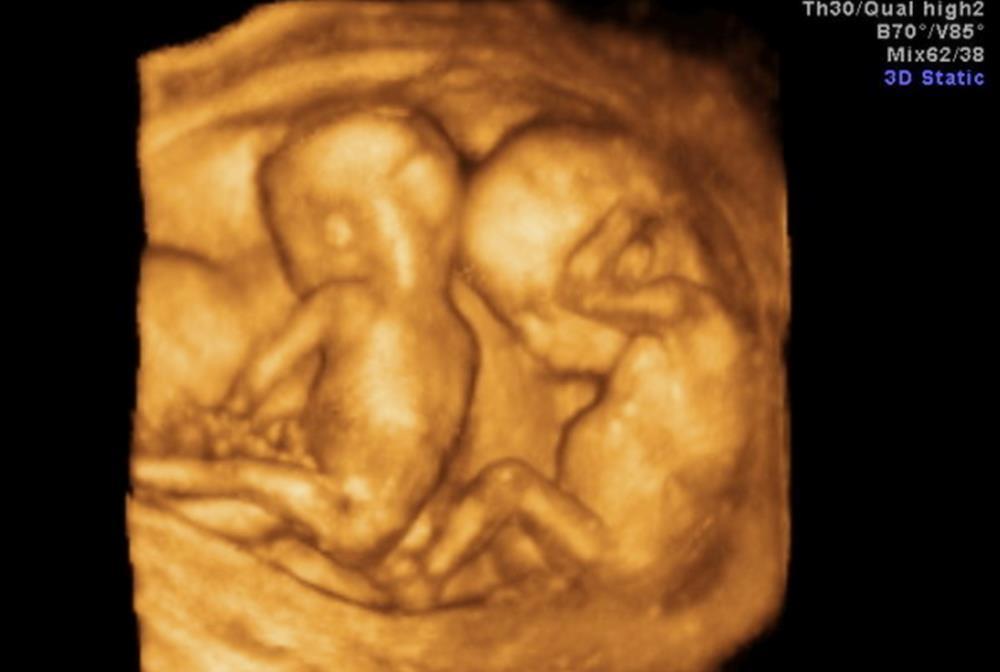

一朋友怀了双胞胎,到了做四维检查的日子,本来想着可以看到宝宝的模样,但刚做完就和我们吐槽:

郁闷死了,谁知道双胞胎做四维还要交“双份钱”啊,我都躺在床上了,

医生一看是双胞胎,赶紧催促我再交一份钱,交完钱医生才给看的。

需要说明的一点是,双胞胎并不是每次检查都收“双份钱”,有明确规定:彩超常规检查按部位收费,中晚期妊娠胎儿检查,计价单位为“每胎儿”。

所以说,在中晚期的检查中,才会收双份钱。